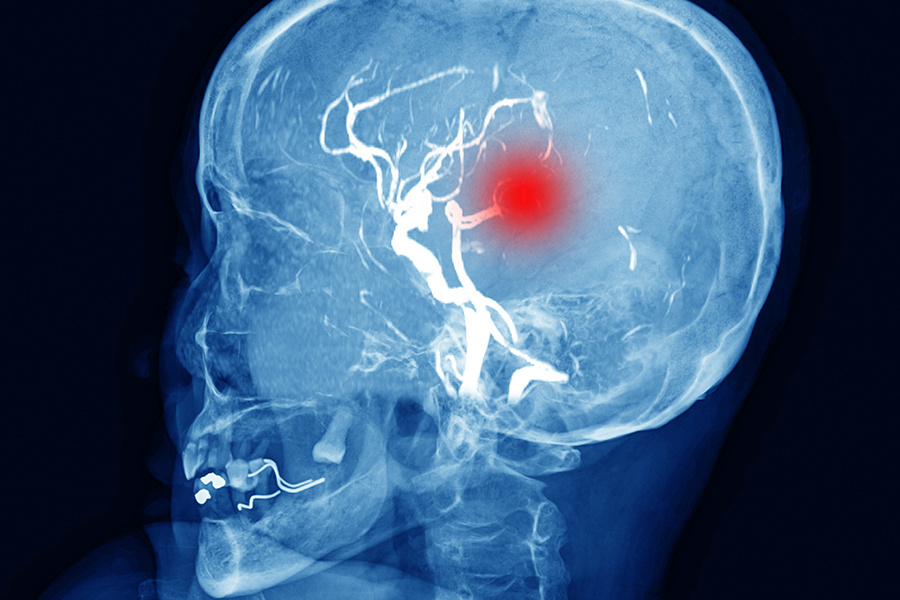

В такой густой крови легко образуются тромбы — сгустки, которые могут закупорить сосуд и перекрыть доступ кислорода к участку мозга. Это ишемический инсульт, который чаще всего случается в первые дни после резкого прекращения пьянства.

Но есть и другая, не менее страшная опасность. Под действием алкоголя сосуды сначала расширяются, а потом резко и надолго сужаются. Их стенки теряют эластичность и становятся хрупкими. На фоне скачка давления такой сосуд может не выдержать и разорваться.

Кровь изливается прямо в мозг, сдавливая его ткани. Это геморрагический инсульт, или кровоизлияние в мозг. Он часто происходит прямо на высоте запоя, когда давление зашкаливает.